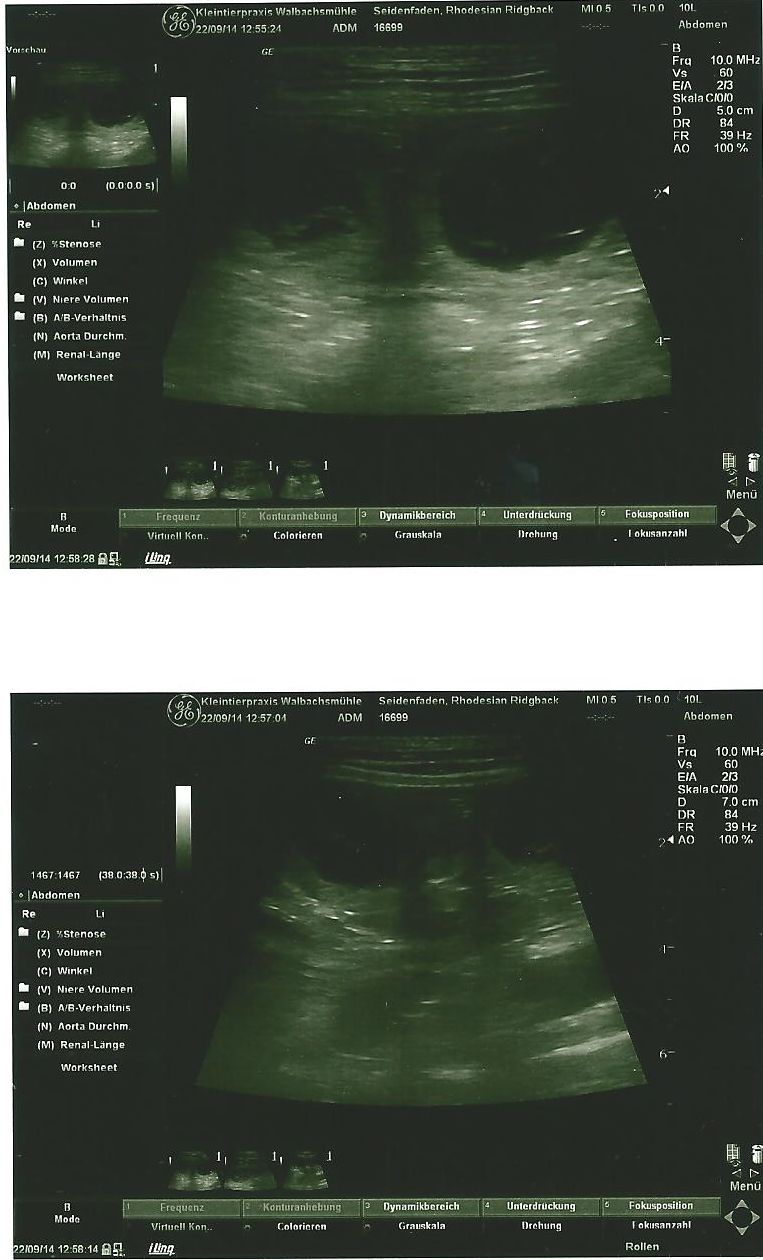

27. Tag: Da sind sie, unsere kleinen Avondales. Heute morgen sind wir zum Ultraschall gefahren. Ich bin fast geplatzt vor Spannung, als ich im Wartezimmer mit Senta saß. Ich habe mir gar nicht vorstellen können, was für eine riesige Freude ich empfinden würde, wenn ich die kleinen Bläschen auf dem Bild sehe. Und dann waren sie da! Wie kleine Perlchen zeigen sich die Babys in ihren Fruchtbläschen. So ein unglaubliches Glücksgefühl erfüllt einen, wenn man das sieht. Ich wusste im ersten Moment nicht, ob ich weinen oder lachen muss :-).